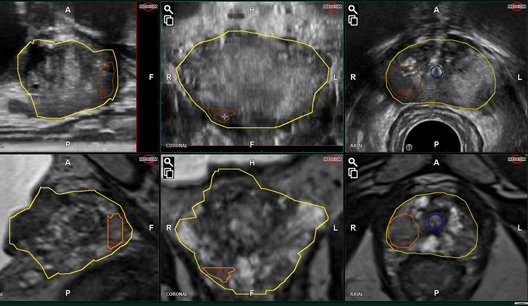

Konturlama Modülü

Çeşitli izleme yöntemleriyle basit konturlama

3D ABD Satın Alma Modülü

Gerçek zamanlı Hız göstergesi, uygun 3D Ultrason Hacmi verisinin alınmasına yardımcı olur.